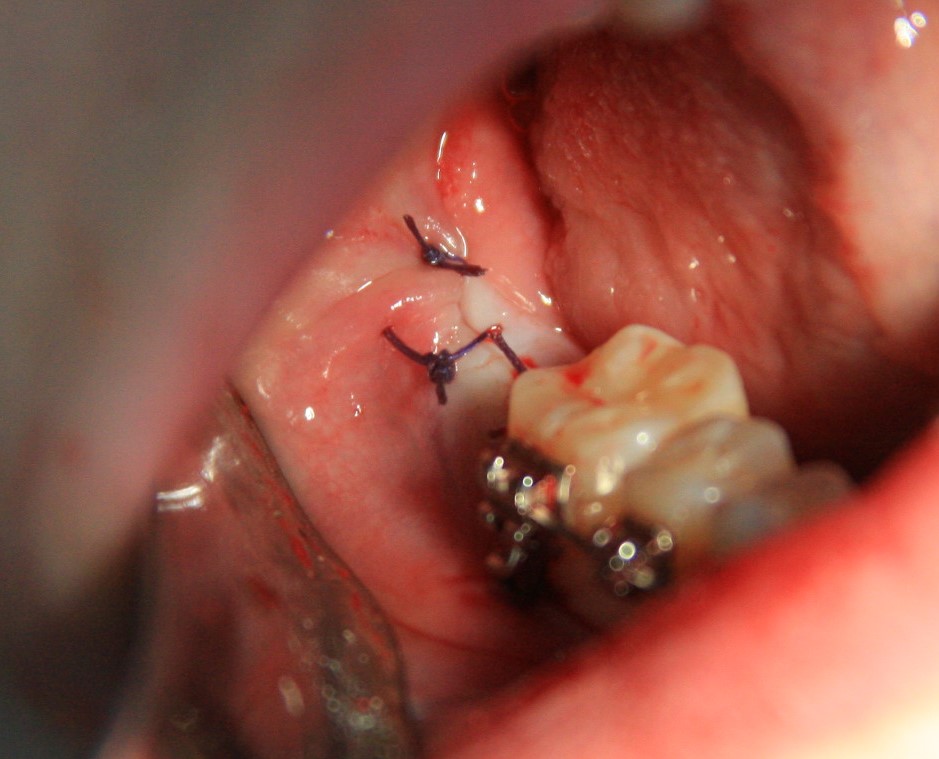

Все. зуб удален. Осталось наложить швы. Лунка зуба зашивается наглухо:

Делаем контрольный снимок, чтобы убедиться в том, что мы не повредили семерку: